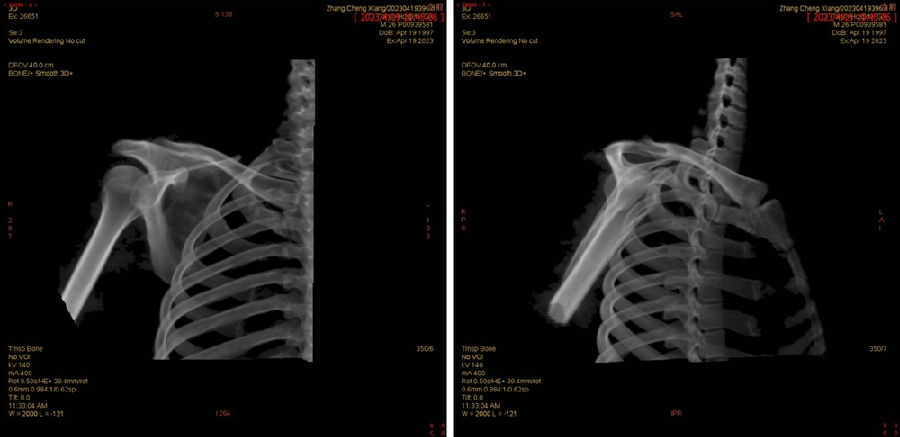

Case1:影像学评估病例,19岁,打篮球摔伤脱位。

图23 首次脱位

图24 打球再次受伤,复发脱位

图 25-27 MRI

双侧CT三维扫描显示:健侧肩胛盂宽度D=25.9,患侧D=23.9,患侧肩胛盂骨性缺损d=6.2,骨性盂唇缺损面积d/D为23.9%(<25%)。肩胛盂轨迹GT(83%D-d)为15.3mm。

图28双侧CT三维扫描

图29 Hill-Sachs间隙为13.8mm(<15.3mm)

图30 评估结果

评估报告提示:右肩胛骨关节盂前下缘撕脱骨折,符合骨性bankart损伤。右肱骨头后上缘凹陷骨折,符合Hill-Sachs损伤。Hill-Sachs间隙为13.8mm(<15.3mm),为轨迹内肩关节前脱位。